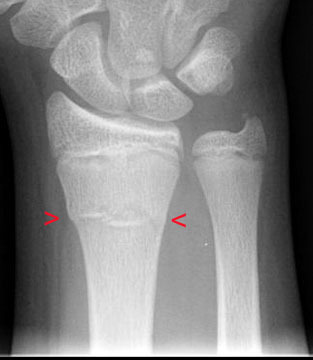

What’s Buckle’s fracture?

Buckle’s fracture

What’s that?